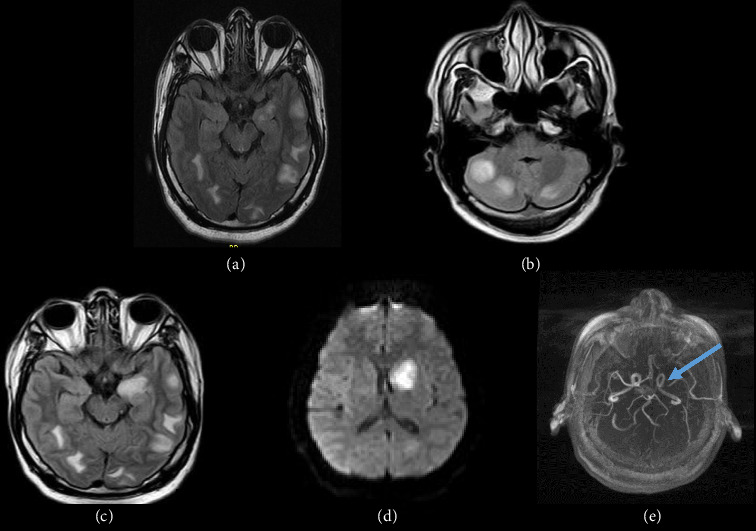

前言:结核治疗期间的矛盾反应的特点是先前存在的结核病变的临床或放射学恶化,或在适当的TBC治疗后出现新的表现。识别这种现象是至关重要的,因为它可能被误认为是治疗失败或复发。尽管在免疫重建炎症综合征后的HIV患者中有广泛的报道,但关于HIV阴性患者的文献很少。病例系列:我们报告了三例免疫功能正常的中枢神经系统结核(CNS-TBC)患者,他们在适当的TBC治疗后出现了矛盾反应。这些包括不同的临床和放射表现,如持续性头痛、结核瘤的出现或进展、脑梗死和脊髓炎。从抗tbc治疗开始平均2.5个月内发生矛盾反应。结论:我们的研究结果强调了密切监测抗tbc治疗后患者的重要性,以迅速发现潜在的并发症。在进行彻底的鉴别诊断时,应考虑到对结核分枝杆菌复合体抗原的过度免疫反应引起的矛盾反应,包括其他中枢神经系统感染、肉芽肿或肿瘤疾病、治疗失败或治疗相关毒性。在这种情况下,确保充分坚持抗tbc治疗和免疫抑制剂至关重要。

Introduction: Paradoxical reactions during tuberculosis (TBC) therapy are characterized by clinical or radiological worsening of preexisting tuberculous lesions or the appearance of new manifestations following appropriate TBC treatment. Identifying this phenomenon is crucial, since it can be mistaken with treatment failure or relapse. Although widely described in HIV patients following immune reconstitution inflammatory syndrome, the literature on HIV-negative patients is scarce. Case Series: We present three cases of immunocompetent patients with central nervous system tuberculosis (CNS-TBC) who developed paradoxical reactions following appropriate TBC therapy. These included diverse clinical and radiological manifestations, such as persistent headaches, apparition or progression of tuberculomas, cerebral infarcts, and dorsal myelitis. Paradoxical reactions occurred within an average of 2.5 months from the start of anti-TBC treatment. Conclusion: Our findings underscore the importance of closely monitoring patients following anti-TBC treatment to identify potential complications rapidly. Paradoxical reactions due to exaggerated immune response to Mycobacterium tuberculosis complex antigens should be considered in a thorough differential diagnosis including other CNS infections, granulomatous or neoplastic disorders, treatment failure, or treatment-related toxicities. Ensuring adequate adherence to anti-TBC treatment and immunosuppressants is essential in such cases.